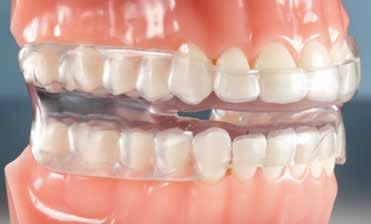

Az Essix retainerek, az egy fogívre kiterjedő mélyhúzott sínek, valamint a felső és alsó frontfogakra orálisan ragasztott fix retainerek mellett, a harapás sagittális rögzítésében elengedhetetlen szerepe van az ún. Pitts Izom Tréning Splint-nek, amelybe a páciens élharapásban összeharap, így az megakadályozza az alsó fogsor visszamozdulását a disztálharapásos helyzetbe (13. kép)